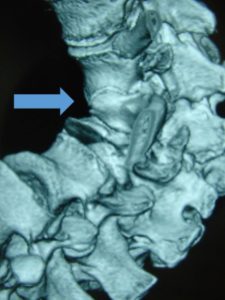

Εικόνα 14 (α,β,γ) : Αξονική τομογραφία Σπονδυλικής Στήλης που παρουσιάζει συγγενείς μεικτές ανωμαλίες σχηματισμού και διαχωρισμού των σπονδύλων καθόλη την έκταση της Σ.Σ.

α) Εγκάρσια τομή

β) Οβελιαία τομή

γ)Μετωπιαία – στεφανιαία τομή